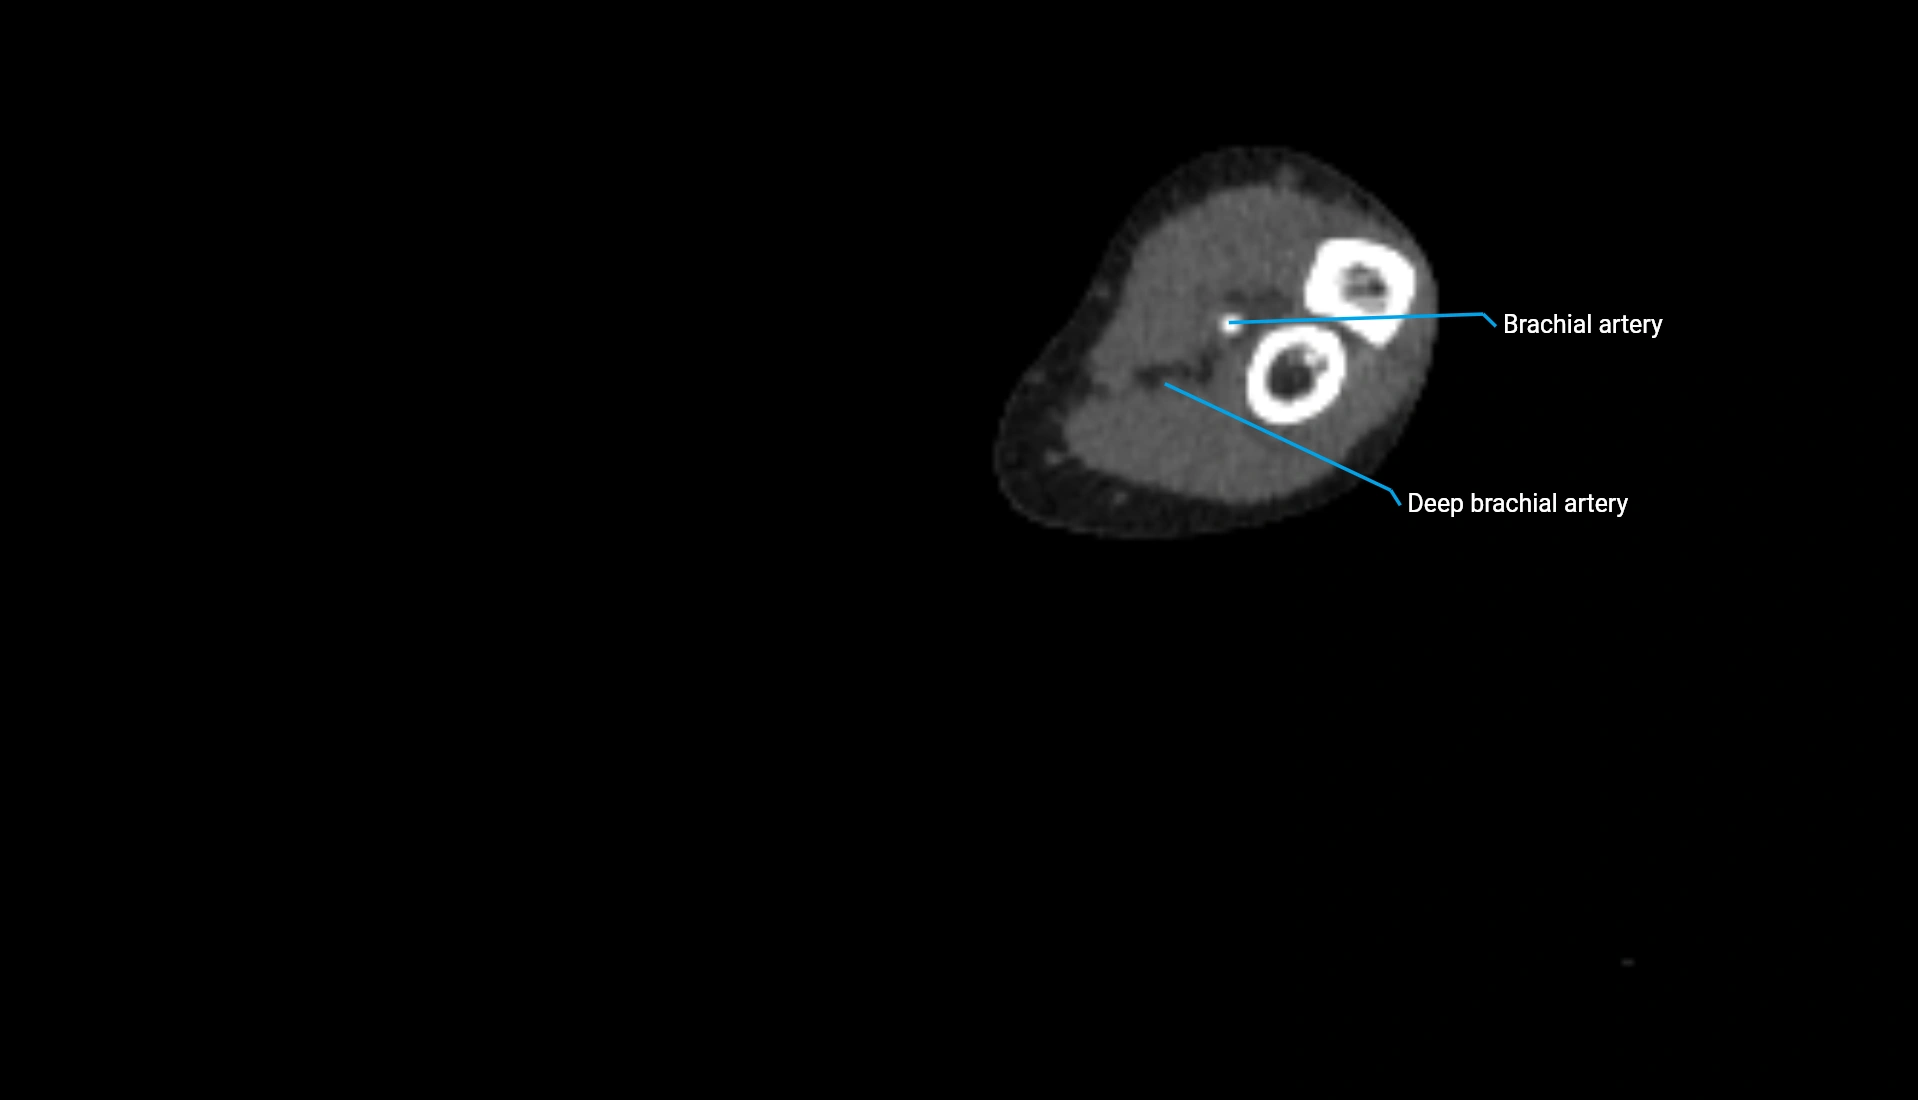

CT Appearance

Non-Contrast CT:

• Cortex: High-density, sharply defined

• Subchondral bone: Dense cancellous matrix

• Articular surface: Smooth concave contour articulating with the capitellum

• Excellent for evaluating bone integrity, alignment, and subtle fractures